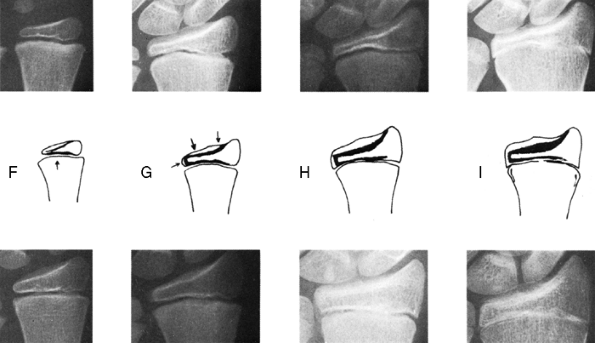

rate of growth either by direct injury to the cells responsible for

growth or by formation of a bony bridge that tethers the epiphysis to

the metaphysis. Salter and Harris provided a classification of

fractures of the physeal plate that is useful in anticipating the

effect of fractures on future growth (49). This classification is shown diagrammatically in Figure 29.14.

Fractures can wander through all zones of the plate, but tend to pass

through the zone of cell hypertrophy where the material is weakest and

the amount of material is least. The material in that zone is

cartilage, which is weaker than bone, and because the cells there are

large, the ratio of matrix volume to cell volume is low (Fig. 29.15).

It is important to note that this part of the plate is the site of

conversion of cartilage to bone, but it is not primarily responsible

for growth that occurs by virtue of cell multiplication and matrix

production in the zones nearer the epiphysis.

the growth zone, they are less likely to interfere with growth than

other fractures are. Both types of fractures, however, may be

associated with a crush injury, which injures the cells by compression.

This mechanism may account for the higher than expected incidence of

growth disturbance in type II fractures of the weight-bearing bones,

such as the distal femur, where growth arrest is found in more than one

third of patients (50). Type III and IV

fractures do, however, cross the growth zone and are therefore more

likely to result in growth arrest. The type IV fracture, in particular,

can result in a bony bridge when the fracture fragment displaces in the

diaphyseal direction (Fig. 29.14). This is one

reason why these fractures must be anatomically reduced. Type V

fractures can occur in isolation or can accompany any of the other

types of fractures. Type V fractures are insidious because they are not

initially recognizable on radiographs and they always demonstrate their

presence by a disturbance of growth, either a shortening or

a

combination of shortening and angulation, usually in the first year

after the occurrence of the fracture. Although the fracture

classifications provide guidelines about the likelihood of growth

arrest, the orthopaedic surgeon must be wary of giving a definite

prognosis for a given epiphyseal fracture until enough time has elapsed

to rule out a type V injury.

![]() |

|

Figure 29.14

Salter-Harris classification of epiphyseal fractures. Fractures of types I and II do not cross the part of the growth plate that is responsible for growth, whereas those of types III and IV do. In the type IV fracture, approximation of epiphyseal bone to metaphyseal bone can result in formation of a bony bridge. (From Salter R, Harris W. Injuries involving the epiphyseal plate. J Bone Joint Surg 1963;45A: 587–622.) |